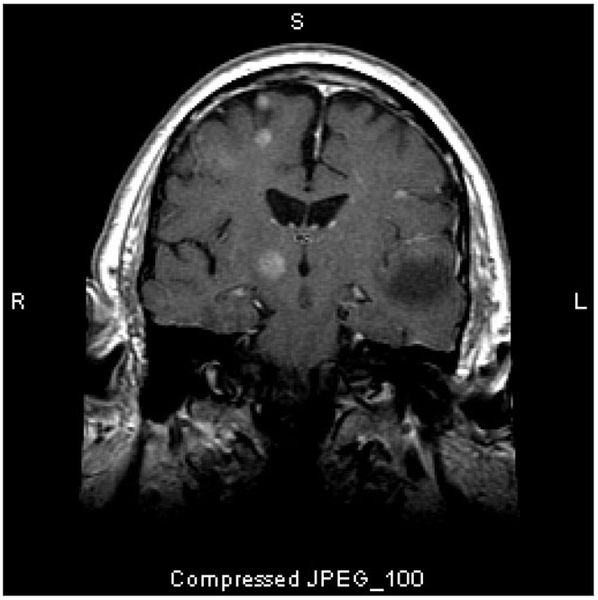

Esta RM muestra múltiples lesiones cerebrales, que representan tumores metastásicos. Más del 80% de las metástasis cerebrales son múltiples.

Imagen cortesía de William R. Shapiro, MD.